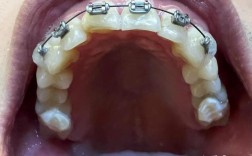

医生的技术与经验:矫正效果核心取决于医生,需考察医生从业年限(建议5年以上)、主攻方向(是否为正畸专科)、案例数量(尤其是与自己牙齿情况类似的案例,如骨性错颌、深覆合等复杂病例),以及是否擅长自己倾向的矫正方式(如传统托槽、隐形矫正、自锁托槽等)。

先进的设备与技术:数字化矫正已成为主流,优先选择配备口内扫描仪(替代传统取模)、CBCT(用于复杂病例分析)、数字化方案设计软件(如3D模拟矫正效果)的医院,能提升精准度和舒适度。